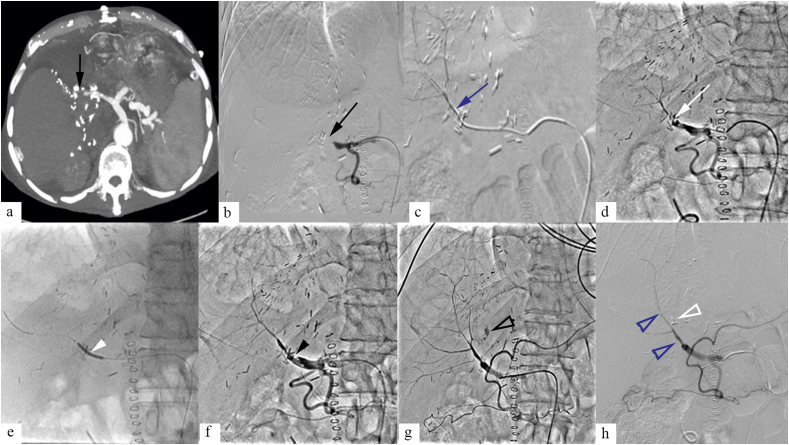

Figure 1.

A 44-year-old male patient, presenting with graft dysfunction at postoperative day 8 of liver transplantation. Contrast enhanced CT (a), and digital subtraction angiogram (DSA) (b) showed hepatic artery thrombosis (HAT) (black arrow). Catheter directed thrombolysis (CDT) was done for HAT (c). DSA at 24 h of thrombolysis (d) showed hepatic artery stenosis (HAS) at the anastomotic site, for which balloon angioplasty was done (e, white arrowhead). Postangioplasty DSA (f) showed residual HAT (black arrowhead). CDT was continued for 12 h, following which DSA was done which showed resolution of HAT, and improved hepatic artery flow (h, blue open arrowhead). However, arterial extravasation was noted along the hepatic cut surface (g, black open arrowhead), for which selective coil embolization was done (h, white open arrowhead).

Retransplantation is the treatment of choice for early HAT, however, is limited due to scarcity of donor liver. Surgical revascularization procedures can be done; however, it is difficult to treat extensive intrahepatic thrombosis. Surgical revision is preferred in early HAT occurring within 5 days of transplant, unless comorbidities preclude surgery, when endovascular treatment can be done. Endovascular treatment of HAT in 1st week following transplant carries risk of hepatic artery rupture. Endovascular revascularization is often the first line of treatment in HAT occurring after 1 week of transplant (Figure 1).6,11, 12, 13 In patients with late onset HAT, when onset of HAT is gradual, collaterals can develop, perfusing the intrahepatic branches of hepatic artery. These patients may not require endovascular intervention.13

Endovascular treatment for HAT includes intraarterial thrombolysis, with or without balloon angioplasty, and stenting. In comparison with systemic anticoagulation, intraarterial thrombolysis has the advantage of high local thrombolytic concentration, lower thrombolytic dose required, and minimal systemic side effects or hemorrhage risk.11,14,15

Early HAS can be treated with surgical revision or endovascular management; however, endovascular management carries some risk of hepatic artery injury and rupture in early postoperative period.13 Endovascular management is the first line of management for late onset HAS. Endovascular management options include angioplasty (Figure 1) with or without stenting and primary stenting alone. Both techniques are equally efficacious, with similar complication rates.6,17 A 2012 meta-analysis by Rostambeigi et al. showed that both angioplasty and stent placement were equally efficacious, with comparable patency rate.18 A more recent comparative study by Magand et al. showed higher 1 year patency rate with stent (93.8%) than with angioplasty alone (73.5%).19 PTA alone for significant HAS carries risk of dissection and hepatic artery rupture in 7% of patients. Hepatic artery rupture or extravasation can be managed with covered stent placement.20 Use of coronary stent for hepatic artery stenosis is considered as an off-label indication. Following stenting, 75 mg clopidogrel is administered daily for 6 months and 81 mg aspirin daily, indefinitely.13 Surgical revascularization is considered for patients where endovascular treatment is unsuccessful. Retransplantation is treatment of choice, however, is limited by scarcity of liver graft and is reserved for patients where revascularization procedures fail.6

Endovascular management is the preferred treatment in HAP, and surgery is considered in patients where endovascular treatment isn't successful. Stent graft is preferred treatment for extrahepatic HAP where HAP is excluded while preserving hepatic arterial supply. Other less preferred endovascular methods include intra-aneurysmal thrombin injection or coil placement.6,13 Intrahepatic HAP can be embolized with coils (Figure 1) or liquid embolizing agents or by US-guided thrombin injection.13